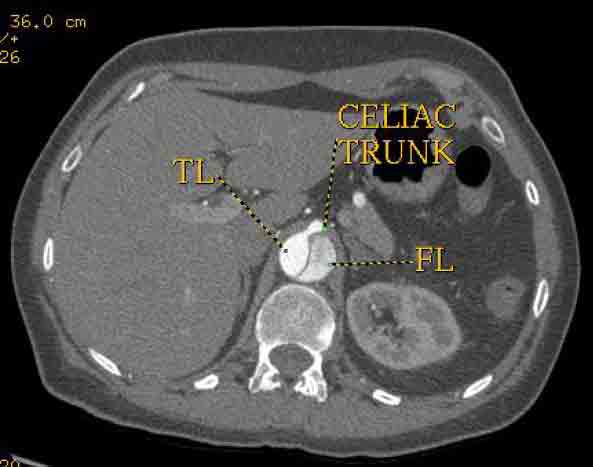

The patient was taken to the hybrid operating suite and a thoracic aortogram was performed. The aortogram confirmed the chronic Type B aortic dissection with a patent false lumen and a fenestration just beyond the left subclavian artery. An intravascular ultrasound (IVUS) was also performed of the entire aortic arch and descending thoracic and abdominal aorta. The IVUS also confirmed that there was an adequate proximal landing zone beyond the left subclavian artery consisting of normal aorta where we would be able to achieve adequate seal of the endovascular stent graft. The septal fenestration began approximately 1.5 cm distal to the left subclavian artery. The true lumen was compressed distally. (Figure 2) The celiac artery appeared to come off the true lumen. (Figure 3) The dissection extended into the superior mesenteric artery and the artery was perfused from both the true and false lumen. (Figure 4) The left renal artery came off the false lumen. (Figure 5) The right renal artery came off the true lumen.